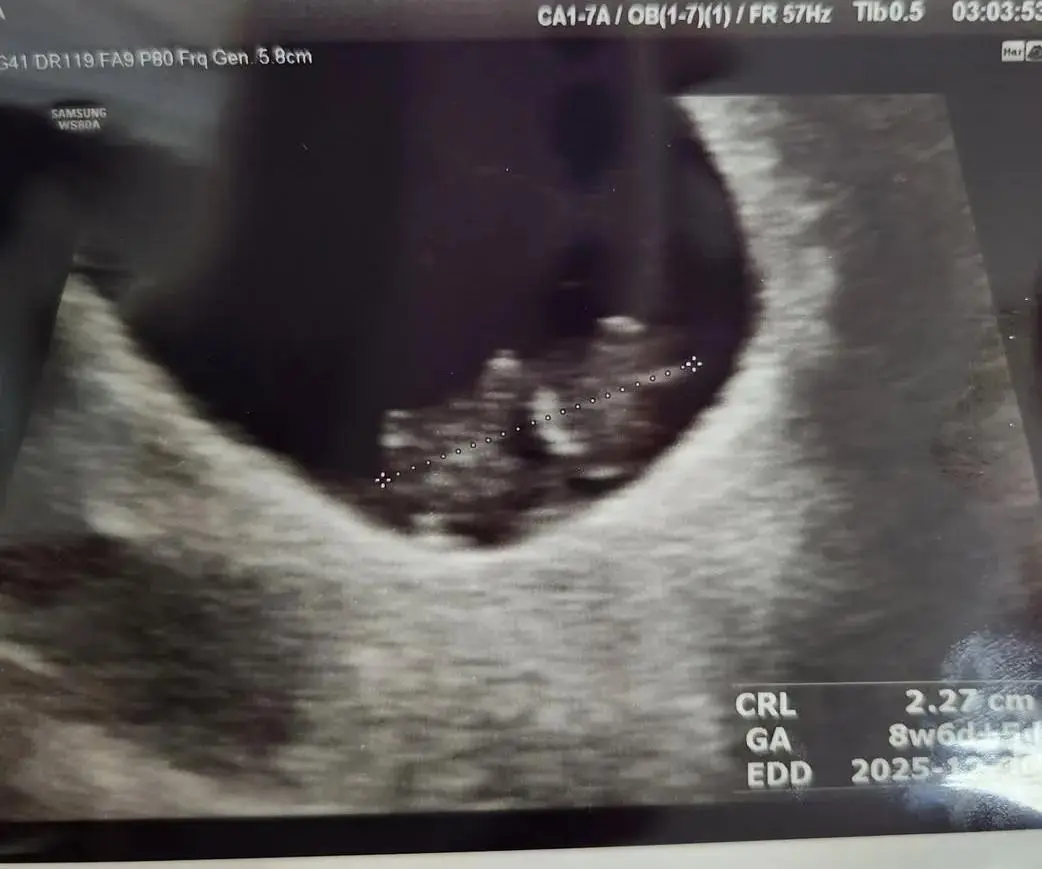

이번 그림은 임신 9주 0일 차, 심장이 멈춘 작은 생명과의 이별에서 시작됐다. 10주 차 정기검진에서 들은 청천벽력 같은 의사 선생님의 계류유산 진단은 내 심장을 쿵 내려앉게 했다. 초음파 사진 속, 조용히 누워 있는 그 아이를 바라보며 나는 몇 주간 눈물로 보냈다. 그러다 존재의 흔적을, 마음의 울림을, 어딘가에 남기고 싶었다.

그림 속 바다는 나의 자궁이고, 물결은 아이를 감싸던 양수이며, 산호처럼 피어난 선인장들은 아이의 생명을 지탱하던 난황을 상징한다. 그리고 그 중앙, 선인장 위에 조용히 앉아 있는 작은 존재는 내가 잠시 품었다가 보내야 했던 아이, '꼬동이'. 꼬동이는 아이의 태명이었다. 음파사진의 꼬동이 모습을 그대로 담았다. 아기는 탯줄로 선인장과 연결되어 교감하며, 양수 속에서 편안하게 떠오른다. 빛은 위에서 쏟아진다. 그 빛은 삶의 시작이자, 이별의 끝이다.